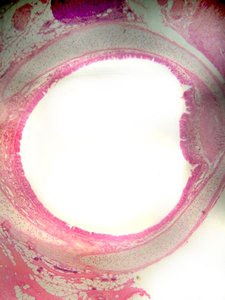

Upper Respiratory Tract Histology

Microscopic Structure

Mucosa: Lined with pseudostratified ciliated columnar epithelium, which helps trap and move particles out of the airway.

Submucosa: Areolar connective tissue containing glands.

Hyaline Cartilage: Provides structural support to the trachea.

Adventitia: Outermost connective tissue layer.

Histology of Respiratory Diseases

Asthma

Bronchial Asthma: Characterized by broncho-constriction and increased mucus production, leading to narrowed airways and difficulty breathing.